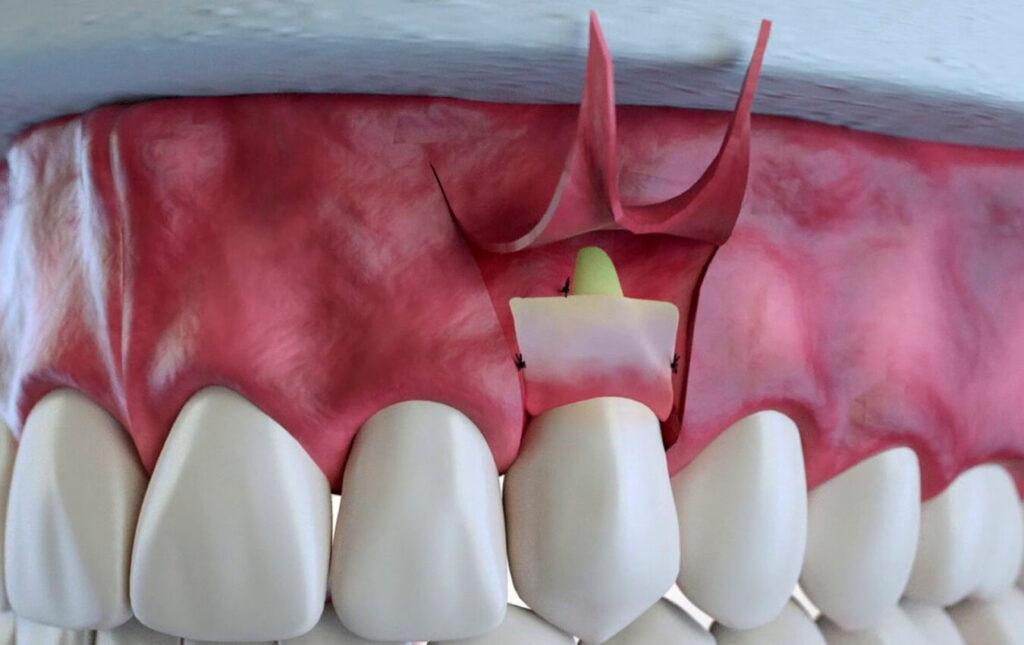

The surgery is performed under local anesthetic. After numbing the certain area, a scalpel will be used to separate the gums from the teeth and then fold them back in the form of a flap. Having now a good access to the roots and bone supporting the teeth, the inflamed tissue is removed. By scaling and root planning the plaque and tartar will be cleaned; bone defects will be eliminated, resulting in smooth edges of the bone. Then, the gums will be placed back against the teeth and anchored in place. A coating is applied over the teeth, serving as bandage, allowing eating soft foods after surgery.